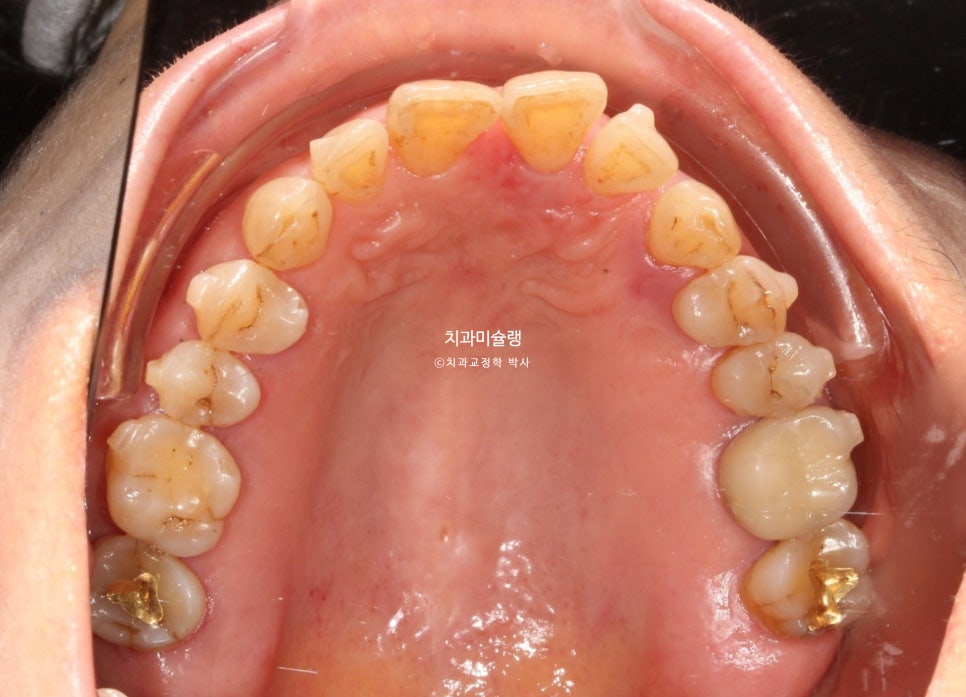

앞니들이 벌어진것 뿐만 아니라 회전된, 소위 “나비치아”입니다.

치료 결과 교합을 계산해 보면 위 앞니 사이 벌어진 공간을 교정으로 무작정 없앴을때 아래 앞니와 심한 교합간섭이 생기는 상황입니다.

위 앞니 4개와 아래앞니 4개 사이즈 합의 비율이 어긋나서 그렇다고 보면 됩니다.

노년교정에서의 중요한 고려사항은 무엇보다 잇몸건강 이죠. 엑스레이상 잇몸이 내려앉은 부분이 여기저기 보이고 뿌리끝 염증이 있는 어금니도 보입니다.